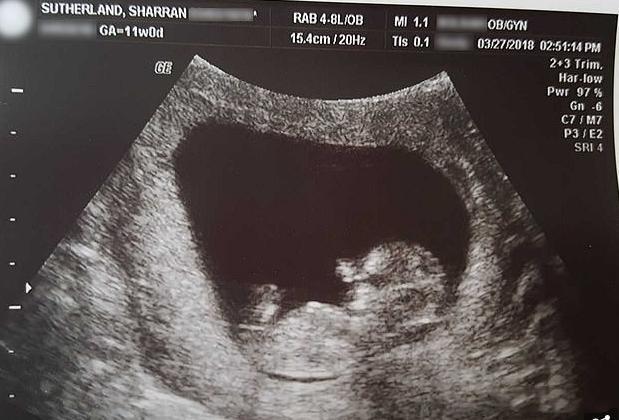

可就在她决定签署领养协议之后,却意外检查出怀孕了,能像其他女性一样可以正常怀孕生子,这一切都让她非常幸福,所以生下一个孩子之后她又生下了第二个孩子,可就在怀第三个孩子的时候出现了意外,她只能被迫流产。孩子被流掉之后,她在网上分享了胎儿的照片,而这张照片触动了所有人。

图片里的孩子仅有10厘米,但手脚都已成型。这一切都打破了大家的认知,有不少人觉得三个月之内的孩子并没有成型,但通过这张照片我们可以清楚看到孩子的脚趾以及手指。其实当胚胎发育到7周时,他们身体中就会出现手臂以及腿,而从第9周开始,我们通过B超也能看出孩子的大概轮廓。萨瑟兰之所以选择分享这样一组照片,是因为她想告诉大家,孩子在母亲体内是如何慢慢形成的,同时也希望大家能够珍惜生命。